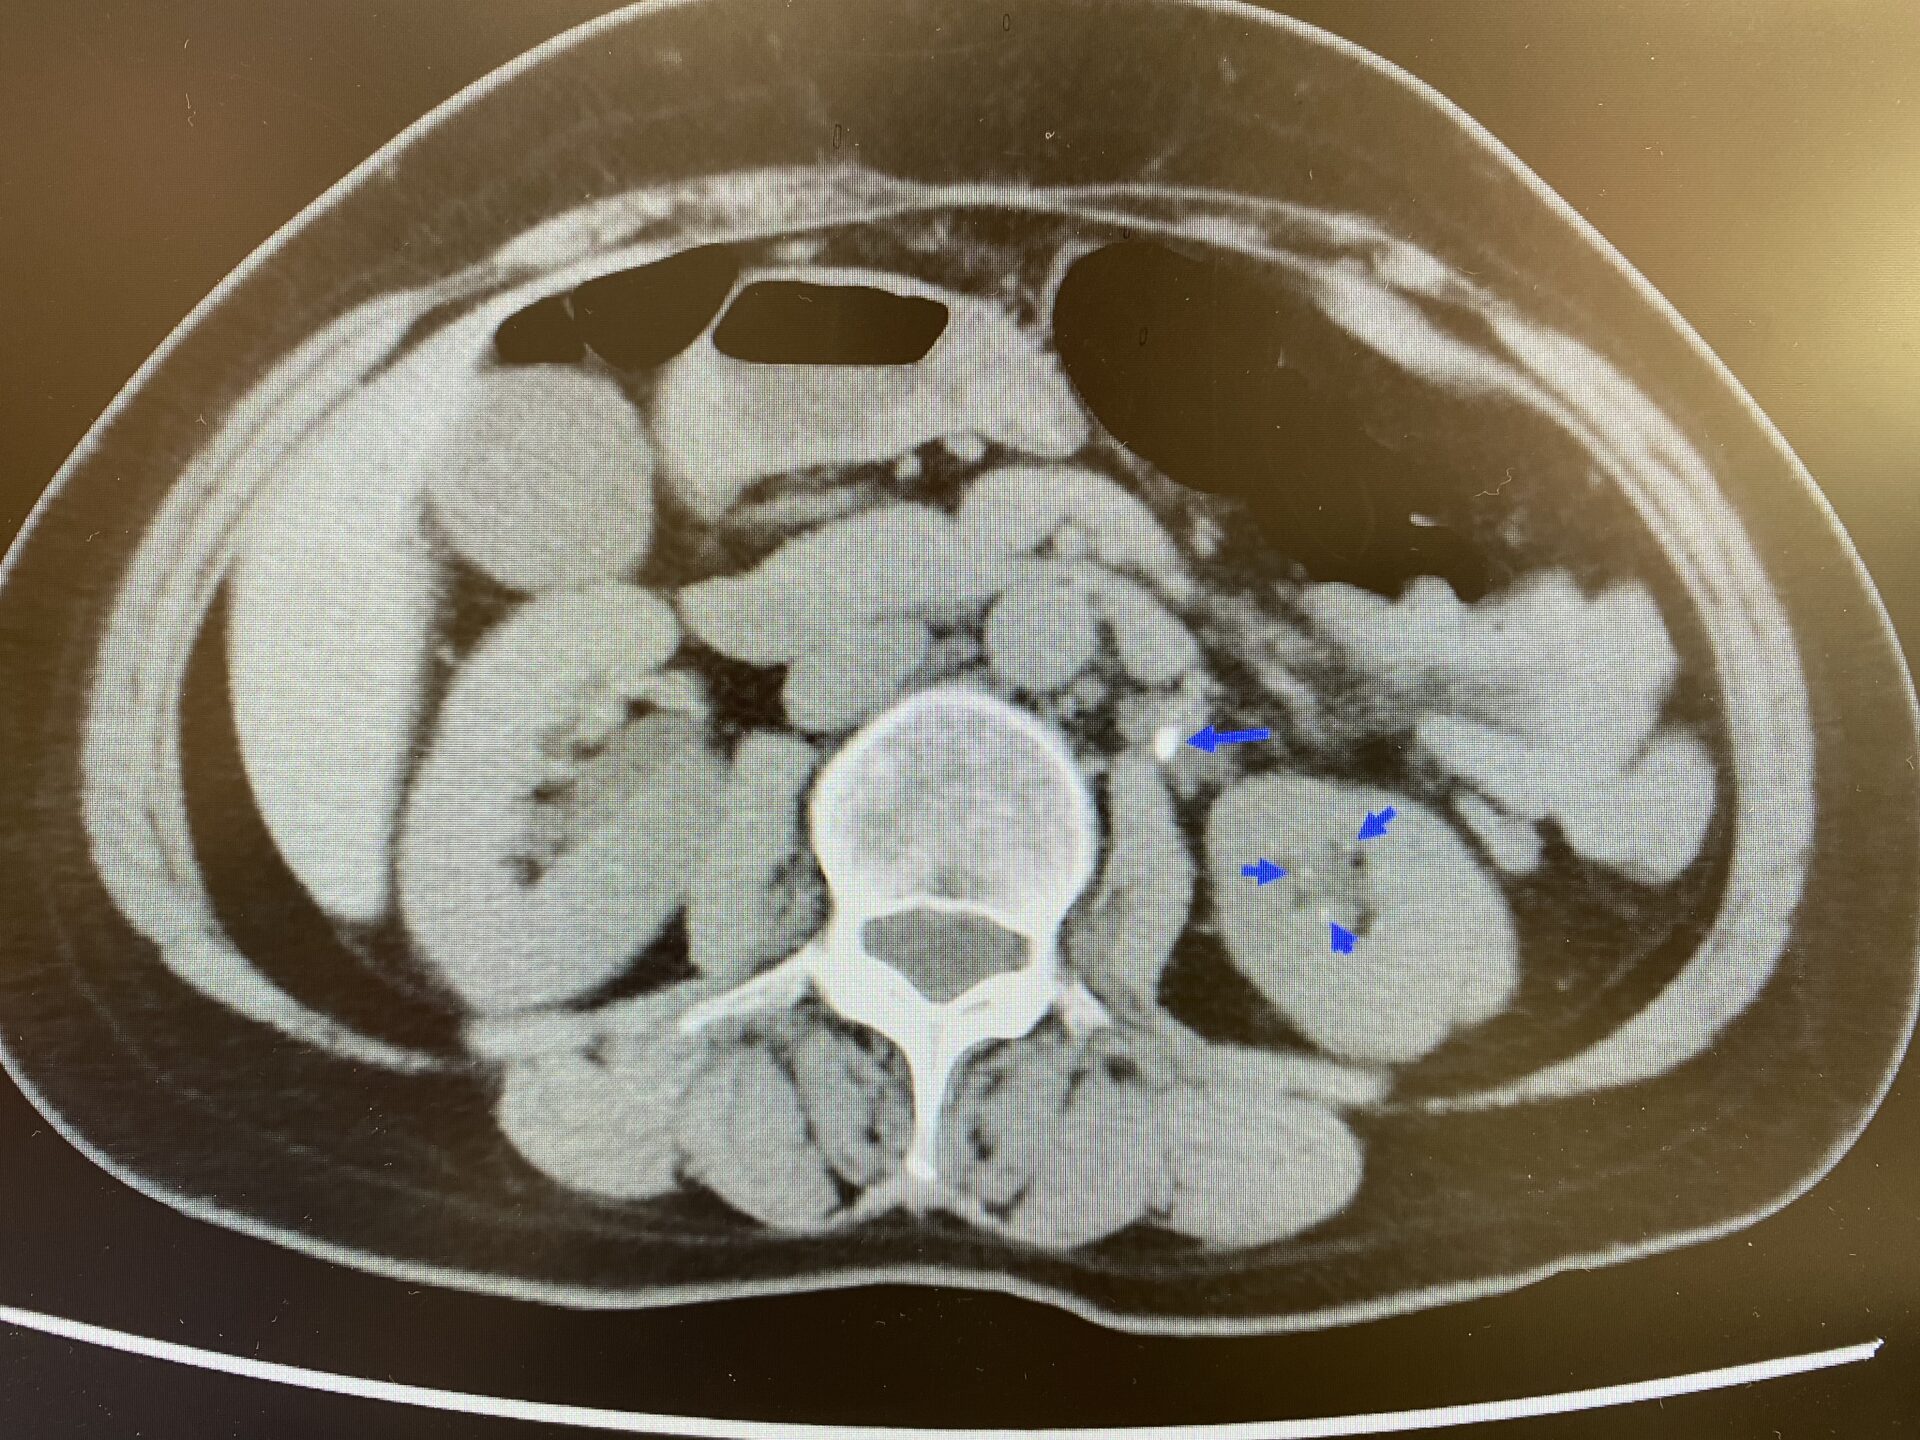

2例目は40歳台男性で、肉眼的血尿と右背部痛を主訴に当院受診されました。エコー、x-p上から両側腎結石および右尿管結石が認められました。

この方はもともと検診でも腎結石を指摘されており、また、多発性に尿路結石を認めていたため、Ca、P含め採血施行したところ、Ca10.6mg/ml(8.4-10.4)、p2.2mg/ml(2.5-4.5)と軽度の高Ca血症と低P血症を認めていました。そこで、intact-PTHを測定したところ、132pg/ml(10-65)と有意に上昇していたため、近隣施設へご紹介したところ、副甲状腺シンチグラフィーで副甲状腺左下腺に集積が認められたため、後日摘除し、病理学的にも腺腫の診断であったとのことでした。